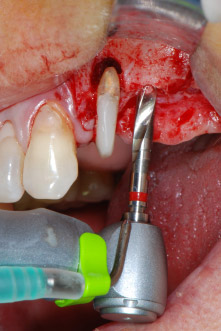

kompletter Verlust von Knochen und Attachment

Abb. 2 und 3: Bei der Freilegung einen Monat nach endodontischer Revision und Beginn einer systematischen Parodontalbehandlung weist die bukkale Wurzel des Zahns 24 einen kompletten Verlust von Knochen und Attachment auf.

Zunächst wurde in einem Versuch, das Paro-Endo-Problem zu lösen, an der verbleibenden Wurzeloberfläche ein vorsichtiges Debridement mit einem piezochirurgischen Gerät vorgenommen (Piezomed, W&H) (Abb. 4); dann wurde der Apex mit dem gleichen Instrument im Sinne einer WSR abgetragen, um das verbleibende infizierte apikale Gewebe zu entfernen (Abb. 5). Eine retrograde Füllung war nicht notwendig, da die orthograde Füllung gerade revidiert worden war.

Brückenpfeiler

Abb. 4: Um den Zahn 24 als vorläufigen Brückenpfeiler zu erhalten, wird das Parodont mit einem piezochirurgischen Sytem gereinigt ...